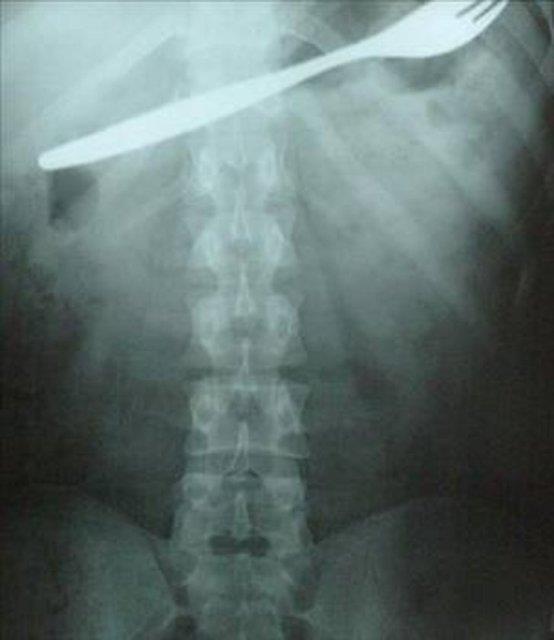

13. Kahramanmaraş'ın Afşin ilçesinde bir genç kız, karın ağrısı şikayetiyle gittiği hastanede, midesinde çatal olduğunu öğrenince şok oldu. Genç kızın çatalı küçük yaşta yuttuğu sanılırken, çatal başarılı bir ameliyatla çıkarıldı.

Kahramanmaraş'ın Afşin ilçesinde bir genç kız, karın ağrısı şikayetiyle gittiği hastanede, midesinde çatal olduğunu öğrenince şok oldu. Genç kızın çatalı küçük yaşta yuttuğu sanılırken, çatal başarılı bir ameliyatla çıkarıldı.